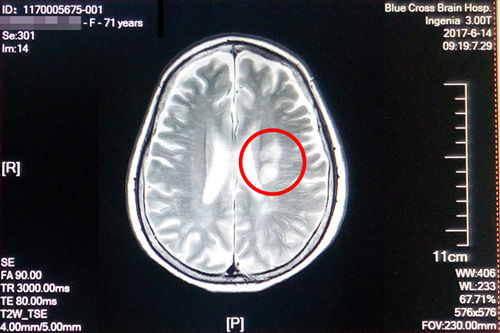

盛阿姨今年五月腦梗復(fù)發(fā),在其他醫(yī)院經(jīng)過治療后有所好轉(zhuǎn),在之后的康復(fù)治療過程中病情又加重了,焦急的家屬聯(lián)系到了“藍(lán)十字”。經(jīng)過神經(jīng)內(nèi)科初步檢查診斷,盛阿姨左側(cè)側(cè)腦室旁腦梗塞(急性期),腦干、雙側(cè)基底節(jié)區(qū)及額、頂葉多發(fā)腔隙性梗塞;大面積腦梗還造成了言語不清和偏癱。入院時,右上肢肌力3級,左上肢肌力4級,雙下肢肌力3級,因此無法行走,病情較重。

術(shù)前磁共振影像顯示:患者多發(fā)性大面積腦梗

更為嚴(yán)重的是,入院后在DSA檢查中還發(fā)現(xiàn)患者左側(cè)大腦中動脈已經(jīng)出現(xiàn)70%以上的狹窄,非常危險。李振并主任解釋,腦血管狹窄是造成缺血性腦血管病的一個重要病因和危險因素,腦血管狹窄使得經(jīng)過腦血管的血液減少,腦細(xì)胞就會缺血死亡。在臨床上,腦血管狹窄程度在50%以下通過藥物治療,在50%-70%之間就要進(jìn)行通過血管介入進(jìn)行腔內(nèi)血管成形術(shù)(球囊擴(kuò)張支架置入術(shù)),而70%以上必須馬上通過血管介入進(jìn)行腔內(nèi)血管成形術(shù)(球囊擴(kuò)張支架置入術(shù)),否則一旦腦細(xì)胞因缺血大量死亡,患者會有性命之憂。